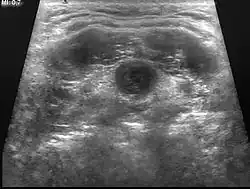

| Ultrasound | Image capture of the degree of mass and its surrounding tissues. |

Thyroid scans and thyroid function studies are often ordered preoperatively; this is important to demonstrate that normally functioning thyroid tissue is in its usual area. An ultrasound of the neck is both inexpensive and effective; CT scans or magnetic resonance imaging are also useful, but not routinely indicated.[10]